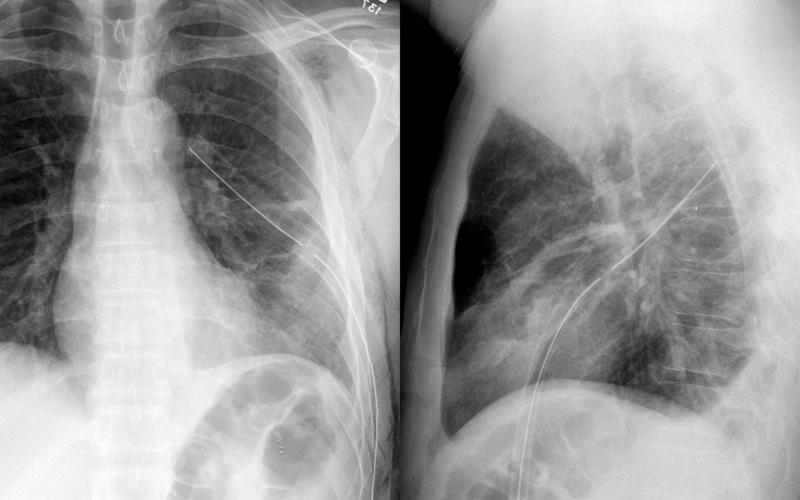

Gallery Pleural chest tube in fissure

chest tube in fissure